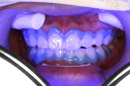

| 色を確認し、同時に比較写真を撮影します | |||||||||